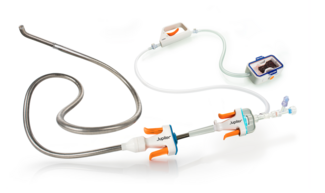

Coronary angiography showed a 70% left main stenosis with TIMI-2 flow down the left system and non-obstructive coronary artery disease in the remaining coronary arteries (Figure 2A). Catheter-induced spasm was less likely, though not impossible. There was no ostial dampening noted on engaging the left main. The 6 French catheter was replaced with a 5 French catheter, but the stenosis persisted. A vasospasm was suspected. The neosynephrine infusion was stopped and followed by administration of 100 µg of intracoronary nitrates. The restoration of blood flow without residual stenosis confirmed the suspected diagnosis (Figure 2B). A bedside echocardiography showed an ejection fraction of 35 to 40%, basal septal and lateral left ventricular wall hypokinesia, severe mitral regurgitation, and moderate tricuspid regurgitation.

In our case, the presence of normal coronary arteries with the exception of the left main stenosis indicated the high probability that this appearance was due to vasospasm. Prolonged coronary spasm may induce endothelial damage, release of vasoactive substances, and platelet aggregation, resulting in local thrombus formation.4 The etiology of the spasm was unclear, but it was unlikely that it was due to the mismatch between the artery and the catheter size, since the vasospasm persisted despite the use of a smaller, 5 French catheter. In addition, a catheter-induced spasm usually appears in cases of size mismatch in an angulated artery, and is seen within 1 mm of the catheter tip, in contrast to the current situation, in which the spasm was diffuse, irregular and eccentric.

In this case, spasm was persistent despite the measures undertaken; therefore, the final step was to inject intracoronary nitroglycerin that dilated the spastic artery, leading to resolution of the ST segment changes, improvement of the left ventricular function, and the blood pressure.

It is important to check for the catheter size, the presence of waveform dampening and the administration of intracoronary nitroglycerin after withholding vasospastic agents. However, in the setting of recurrent episodes of idiopathic vasospasm, few articles have reported revascularization as the ultimate treatment of choice either with percutaneous angioplasty or surgical bypass, in case the combined medical use of nitrates and calcium channel blockers fails to prevent further acute events.11